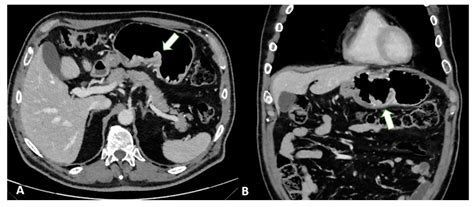

Computed Tomography, commonly known as a CT scan, is an advanced imaging technique that uses a combination of X-ray technology and computer processing to create cross-sectional images of the body. Unlike a standard X-ray, which produces a single flat image, a CT scan takes multiple images from various angles, which a computer then compiles into detailed "slices." This allows physicians to examine organs, soft tissues, bones, and blood vessels with significant clarity.

In the context of cancer detection, a CT scan is often used to:

• Identify the presence, size, and shape of a suspected tumor.

• Determine if cancer has spread (metastasized) to other organs.

• Guide biopsies by providing precise anatomical maps.

• Monitor how a tumor responds to ongoing treatments like chemotherapy or radiation.

While the diagnostic capabilities of modern scanners are impressive, it is a medical reality that a Ct scan will show cancer in most—but not all—cases. The accuracy of a scan depends on several variables, including the size of the growth, its location, and the type of tissue involved. Very small tumors, or those that have not yet caused a significant change in the density or structure of an organ, can sometimes be missed.